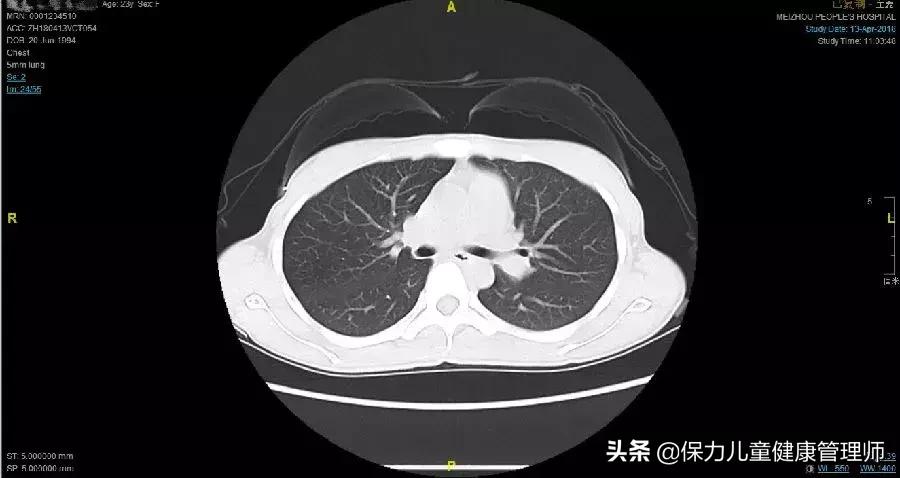

小曾4月13日胸片

双肺、纵隔CT扫描未见明确异常。